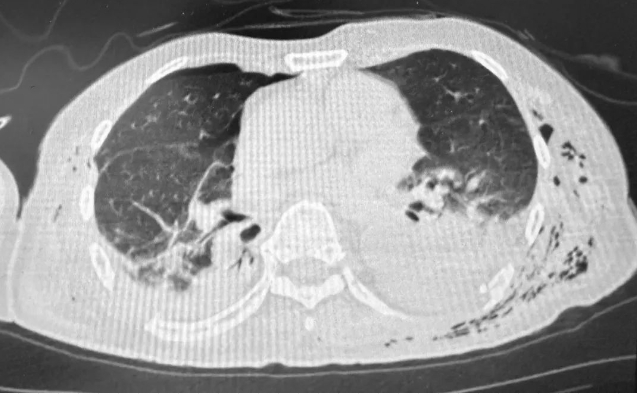

急诊科迅速为老张完善一系列检查。复查胸部CT显示,老张的胸部双侧有大量的创伤性血气胸,右侧第1-8肋骨及左侧第1-11肋骨骨折,双肺挫伤伴有膨胀不全,纵膈、颈部及胸壁皮下广泛气肿。软化的胸壁及大量的血气胸等危重情况,随时可能造成严重的呼吸循环障碍,生命危在旦夕。

▲患者双侧存在大量的创伤性血气胸